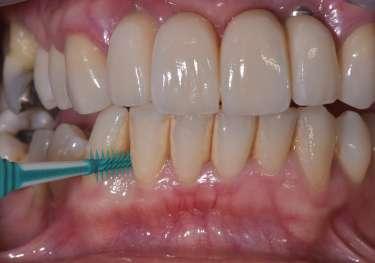

Le innovazioni tecnologiche per l’efficace mantenimento delle riabilitazioni implantari

La prevenzione terziaria è una vera sfida per l’igienista dentale, che per competenza del suo profilo professionale ha la gestione del mantenimento delle riabilitazioni odontoiatriche.

Le terapie riabilitative implantari per pazienti con edentulia parziale o totale, permettono di riportare sia la funzionalità che l’estetica, con una prevedibilità di successo che dipende, oltre che dall’efficace piano terapeutico chirurgico implantare del professionista chirurgo, anche dalla responsabilità attiva del paziente a seguire corretti stili di vita di igiene orale domiciliare e follow-up. Questi devono prevedere la visita diagnostica di controllo dell’implantologo e la visita di controllo dell’igienista dentale. Per sollecitare l’aderence ai follow-up, usare l'automazione workflow e moduli di anamnesi personalizzati (gestionale Alfa Docs) permette una migliore gestione e un monitoraggio efficace delle cure e dei richiami personalizzati in base ai bisogni extra clinici dei pazienti. La vera sfida è il management di igiene orale in pazienti presi in carico che sono stati sottoposti a terapie implantari in altri studi, e che mostrano clinicamente mucosite, con interessamento della mucosa perimplantare o con perimplantite che coinvolge l’osso di sostegno.

L’utilizzo degli scovolini in gomma, (GUM Soft Picks Confort Flex), risultano essere delicati sui tessuti perimplantari, ed efficaci, grazie alle differenti misure possibili, per la personalizzazione della scelta dell’interprossimale a seconda dello spazio sovracrestale.

L’evoluzione di tecnologie così sofisticate ha permesso di poter offrire l’opportunità di fare “la giusta scelta” personalizzata per ogni caratteristica anatomica, di maualità e predisposizione di fragilità, o soltanto seguire l’approccio caratteriale del paziente.

(TBM) Nardi G.M. et al. Tailored Brushing Method (TBM): an innovative simple protocol to improve the oral care. J Biomed 2016; 1:26-31. Il protocollo di igiene orale deve essere personalizzato in base alla tipologia del manufatto protesico implantare, poiché spesso la persona assistita ha difficoltà di efficacia nel controllo del